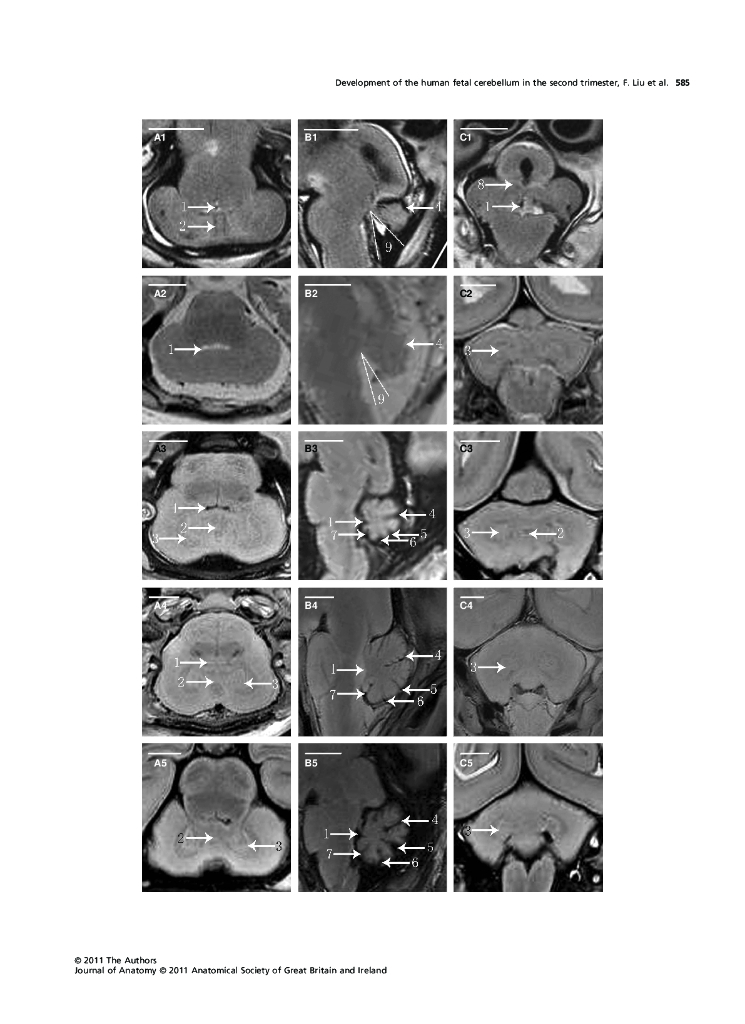

《断层影像解剖学》Development of the human fetal cerebellum.pdf